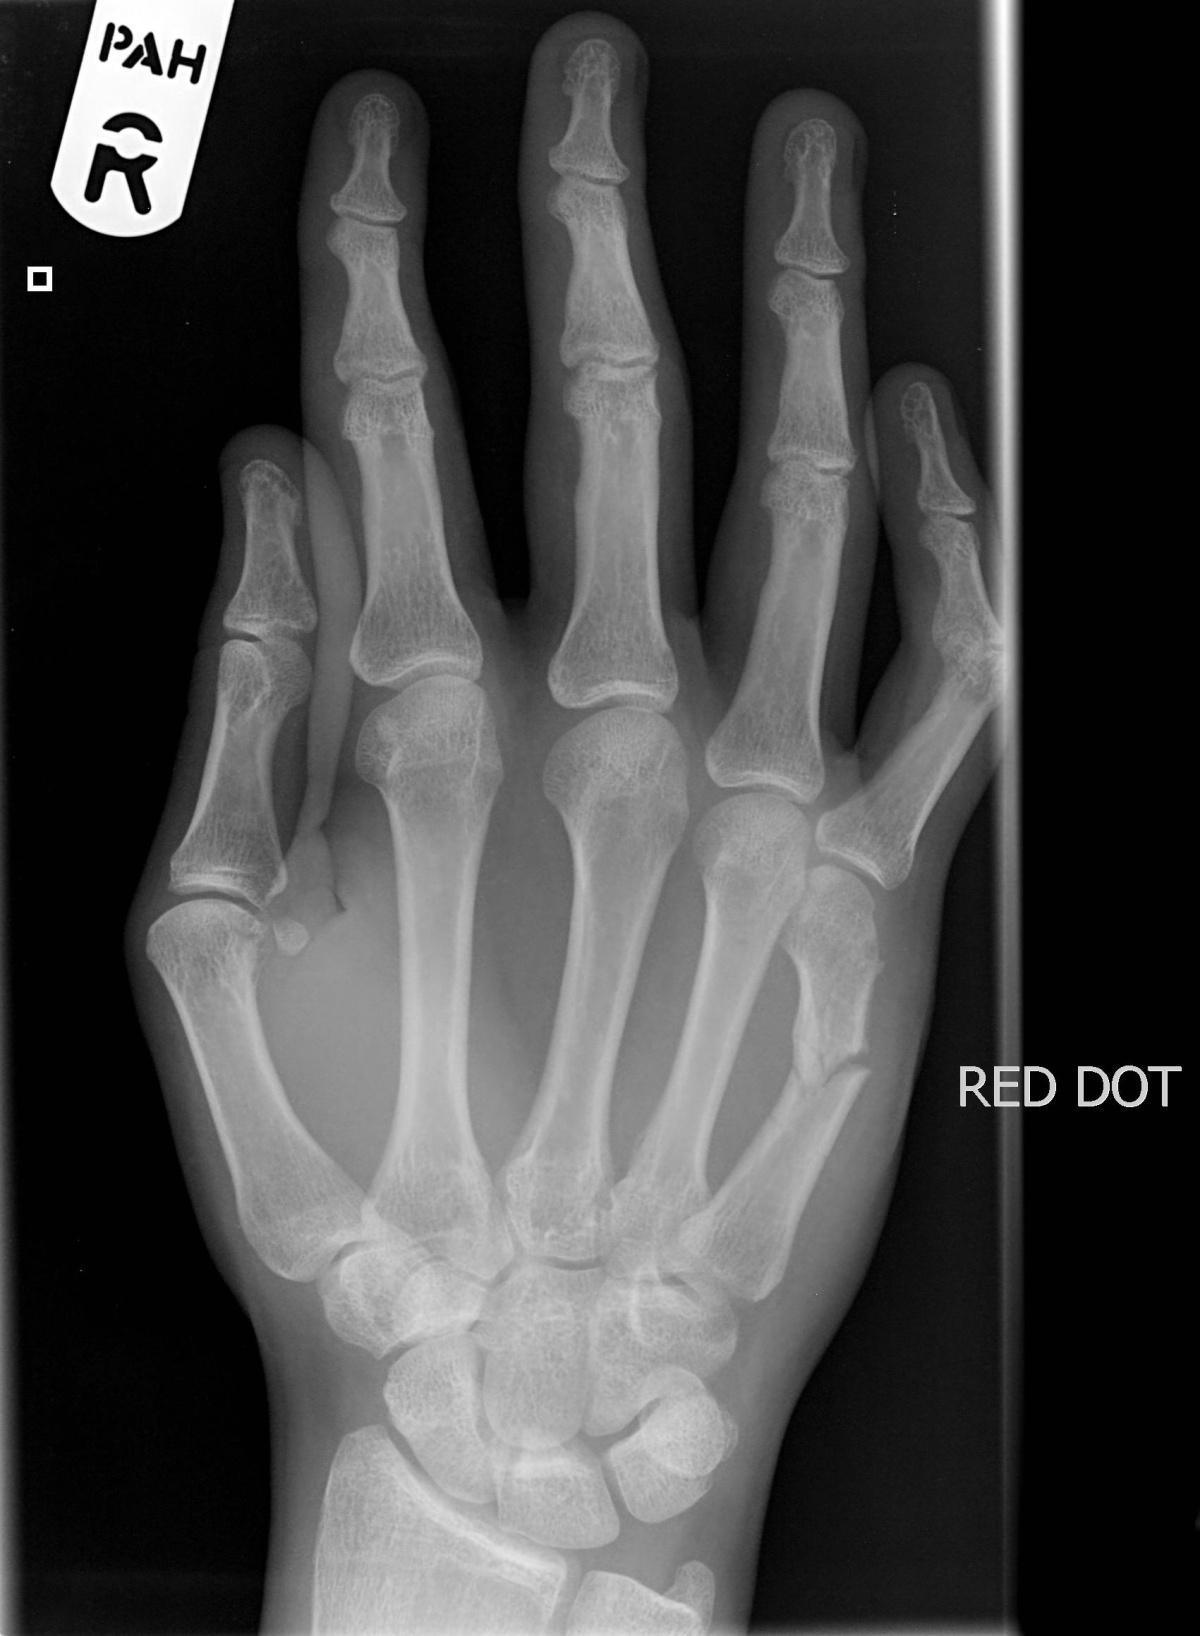

Jeremy Jones, Radiopaedia.org. From the case rID: 6428

Avis chirurgical (Si nuit, plâtre, prévenir interne CMF, Cs lendemain)

Attention si luxation base métacarpiens

Chirurgie, mettre attelle plâtrée poignet + métacarpo-phalangienne en attendant le bloc.